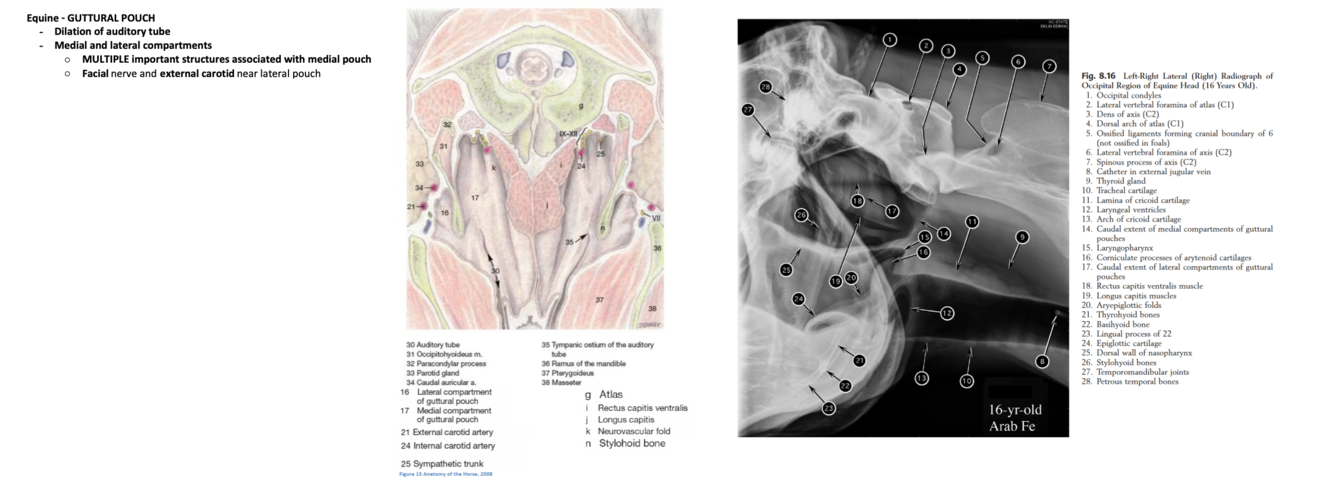

BRIEFLY, details of equine guttural pouch